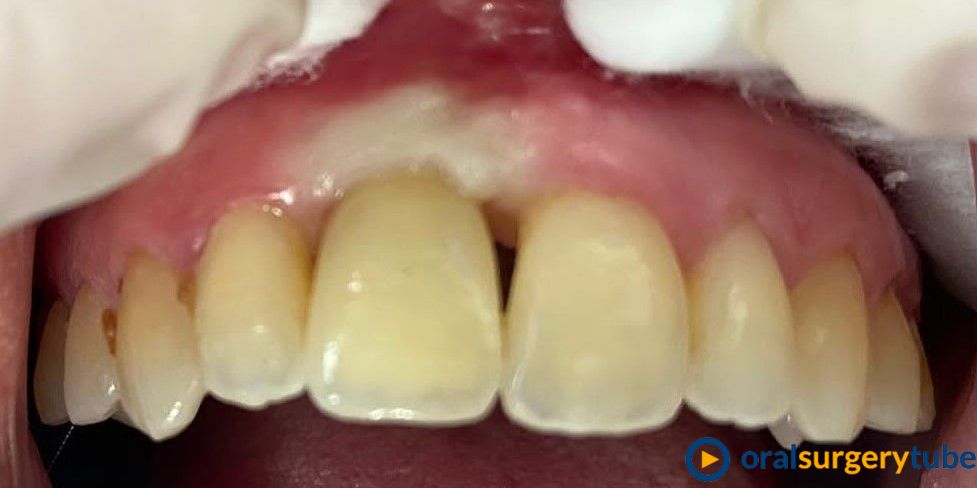

Paciente mujer joven, fumadora y de higiene regular. Con periodontitis moderada estabilizada pero con mal mantenimiento y con un proceso muy avanzado en el 21. Se le realiza en el mismo acto la extracción, legrado y lavado profuso, fresado y colocación guiada del implante con torque de 20N . Y después se regenera el aveolo con mix de autólogo de rama rascado con un micross y Bioss collagen y un injerto de tuberosidad en vestibular. No se hace carga inmediata por la baja estabilidad, se coloca y tapón de cicatrización y periacryl para sellar. Buscando un tratamiento similar (salvando mis infinitas limitaciones y distancias) a los protocolos de actuación de dos gigantes como Mesquita (implanteperio) y/o el de David González y su articulo de 3 Layers para alveolos sin tabla. Me decido por esta opción ya que todo lo que fuese levantar un colgajo sería al 100% un desastre estético y no estoy capacitado para un bloque mixto de tuberosidad ósea y blanda. Quizá haya fallado mi diagnostico o mi técnica.

Aparentemente la cicatrización es buena, asintomático y con buen aspecto. Pero en el control a 4 meses veo muchísima reabsorción de mi regeneración en vestíbulo. Sería por el potencial osteoclástico en ese lecho? o por no poner una capa de reabsorción lenta en la parte más externa?... en unos días probaré a ver si no me quedo con el implante en la mano.